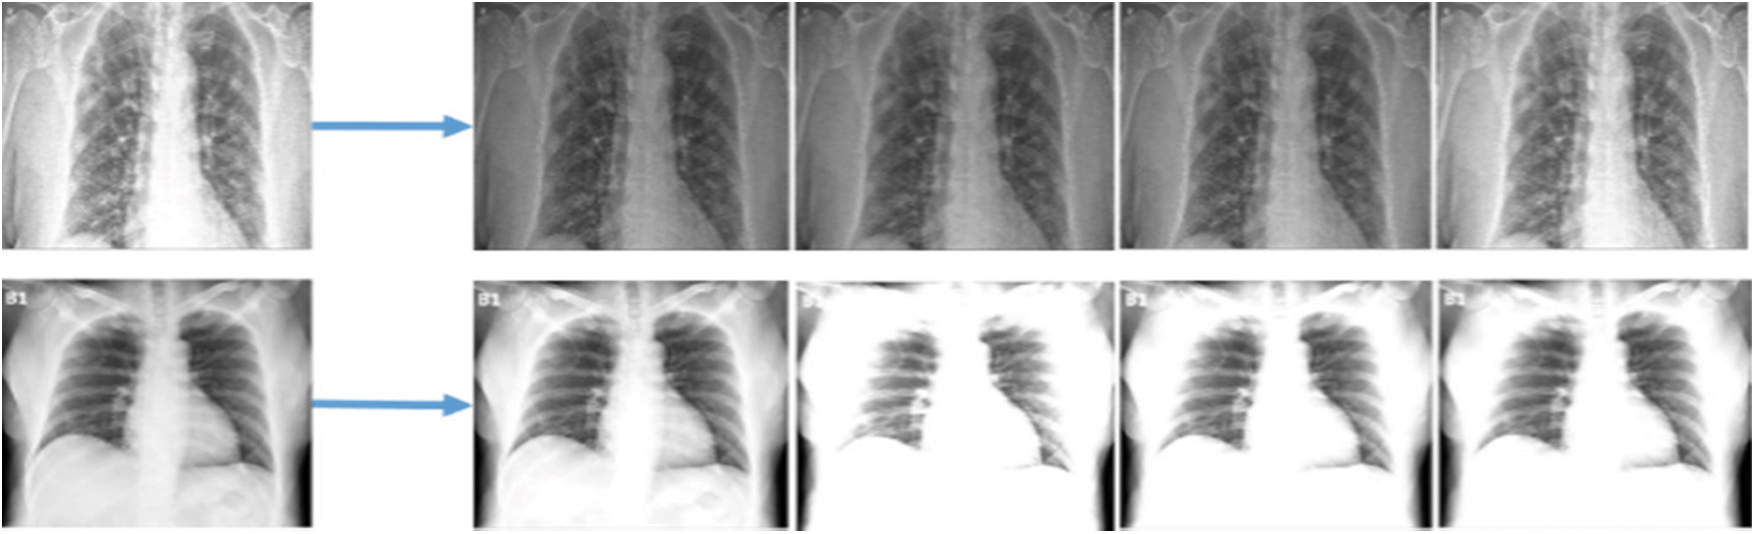

In this section, different aspects were evaluated including the augmentation results and the performance of the classification trained models of the extracted features from the chest X-ray images on the use of raw data. In the original dataset, 1300 images have been shown as normal, and 200 images have been shown as infected of pneumonia, and as such these provide an inaccurate prediction of the COVID-19 sample while testing due to data differences. Fig. 6 shows a screenshot of multiple chest X-ray images based on patients. The pre-processing through deep learning API Keras technique, however, has been used for equalisation and creating variations in brightness in order to make the COVID-19 affected images distinctively clear for understanding. The ultimate results of pre-processing have been to make the conclusive understanding clearer to none experts like clinicians or technicians.

Figure 6: Screenshots of data augmentation of different types of images